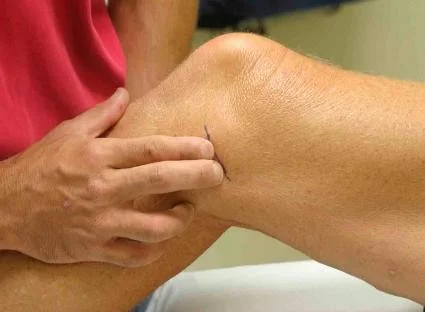

| Feel | Tenderness (General, Localized): Quadriceps, Patella, Patellar tendon, Tibial tuberosity, Origin, and insertion of collateral ligaments, ACL, MCL | Identify areas of pain and inflammation in relevant structures | Tenderness - General: Tenderness - Localized: Medial Structures (Tibial Tuberosity, Joint Line, Medial Tibial Condyle, Patella, Medial Femoral Condyle, Joint Space, MCL): ![]() Lateral Structures (Quadriceps, Patella, Tibial Tuberosity, Head of Fibula, LCL, Lateral joint line): ![]() | Localized pain upon palpation |

| Joint-line tenderness, medial and lateral | Assess for meniscal or collateral ligament pathology | Joint lines: ![]() | Pain upon palpation along the joint line | |